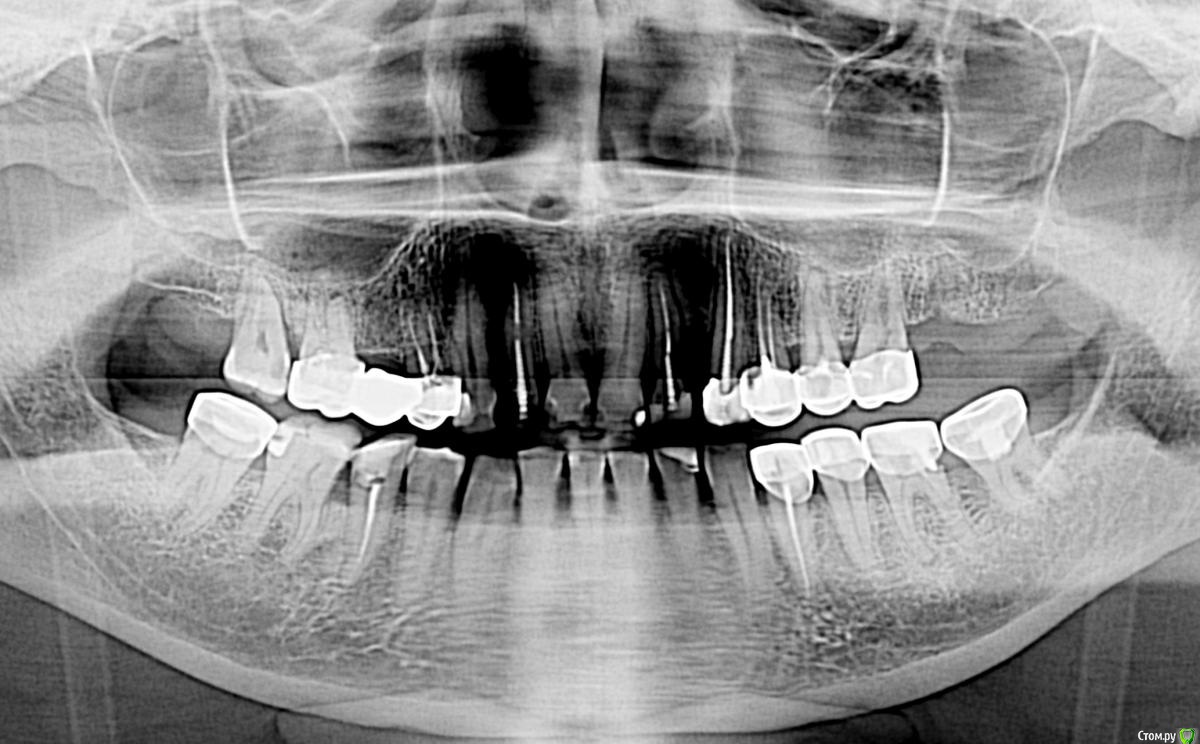

НАТА1976 Опубликовано 26 июля, 2019 Поделиться Опубликовано 26 июля, 2019 Здравствуйте,Поскольку уже второй год мне проводят лечение пародонтоза, но улучшения не наступают. Беспокоят: кровоточивость,припухлость десен, болезненные ощущения и чувство дискомфорта при нажатии в районе носо-губной складки справа. Самостоятельно приняла решение сделать панорамный снимок, но мой лечащий доктор сказал, что такие снимки не читает. И предлагает после окончания курса лечения пародонтоза ставить коронки. В частной клинике, где сделала снимок, утверждают, что нужна операция. Ситуация осложняется тем, что проживая в сельской местности, не имею возможности получить консультацию других специалистов очно. Помогите пожалуйста разобраться в ситуацииЕсть ли кисты на снимке?Нужна ли операция? или удаление зубов?Кто из специалистов занимается такими заболеваниями хирург- стоматолог или это уже челюстно лицевая хирургия? Можно ли подобные манипуляции делать в условиях частной стоматологии? Или лучше попытаться получить направление в краевую больницу. Ссылка на комментарий

сирена Опубликовано 26 июля, 2019 Поделиться Опубликовано 26 июля, 2019 (изменено) Есть киста в области 12 зуба(в переднем отделе справа),если Ваш врач этого не видит и собирается покрыть этот зуб коронкой,это очень печально.Езжайте в город и получите там консультацию нормального врача(стоматолога-хирурга).Слева тоже есть какой то очаг между передними зубами,надо уточнить прицельным снимком или компьютерной томографией. Изменено 26 июля, 2019 пользователем сирена Ссылка на комментарий